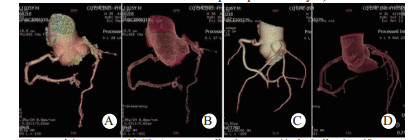

| 图 4 例6 TACS结果(A、B:伤后6 d心绞痛发作时三维CTA示冠状动脉左旋支细小,但腔内无异常密度影; C、D:半年后随访CTA示左旋支已无异常) Fig 4 Case 6 with TACS(A and B: during the attack of angina pectoris after injury 6 days, three-dimensional CTA showed small left coronary artery branch, but no abnormal density shadow in the lumen; C and D: CTA in 6-month follow-up showed no abnormalities in left lateral branch) |